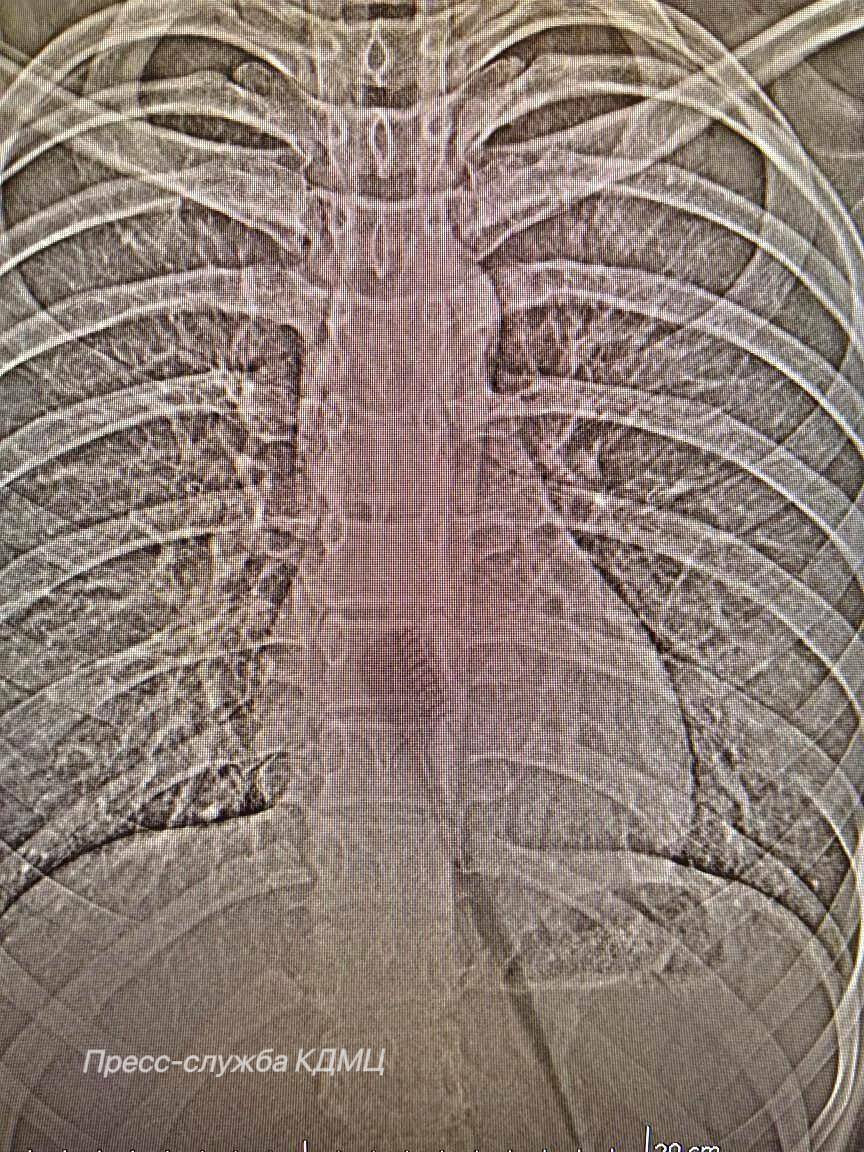

Щётка частично находилась в пищеводе и представляла риск повреждений. Предмет удалили эндоскопически, что позволило избежать осложнений и ускорить восстановление пациентки.